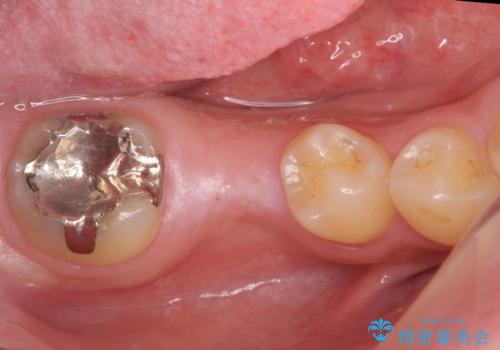

- 右下の奥歯にインプラントを入れたいと来院。

抜歯から時間が経っており、骨が十分あったためすぐにインプラントを入れることが可能でした。骨も補う必要がありませんでした。